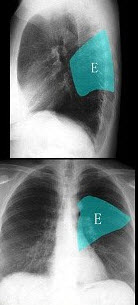

如图,在正常胸部X线影像图像上,该英文字母所代表的肺段为()

A.内基底段

B.前基底段

C.外基底段

D.后基底段

E.背段

点击查看答案